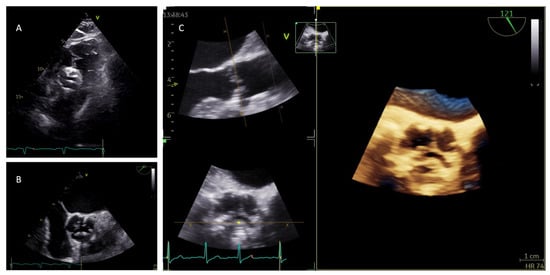

2. Aortic Stenosis Etiology and Echocardiographic Morphologic Assessment

3.2. Role of 3D Echocardiography in the Evaluation of Aortic Stenosis